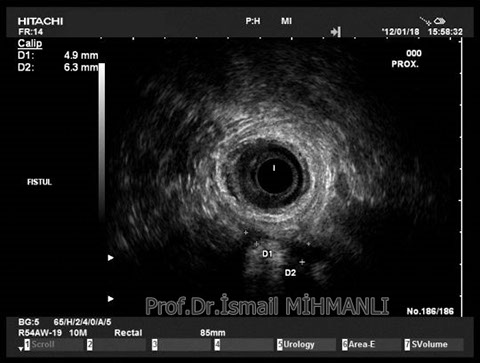

Transsfinkterik fistül

Fistüle makat kası hasarı eşlik ediyorsa endoanal US'de tespit edilir.